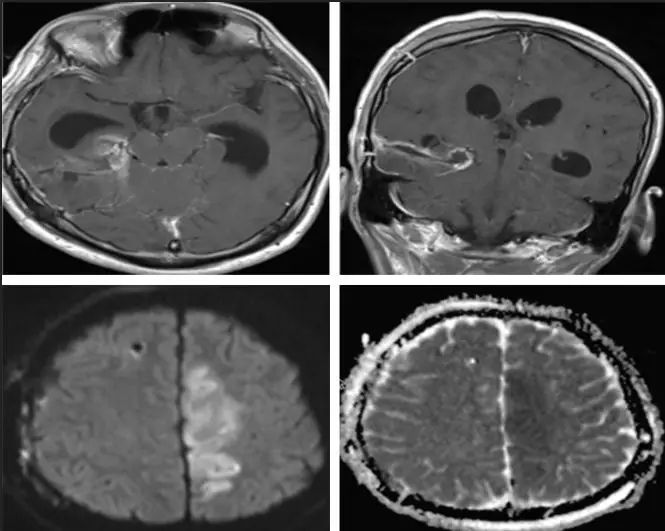

图6.术后2周头颅CT:脑室系统积水及颅内高压进行性发展。 术后1月余,进行性右侧肢体偏瘫失语伴意识不清。查体:昏迷,GCS 1+1+5,右侧瞳孔5mm,对光反射迟钝,左侧4mm,对光反射灵敏。双侧肌力查体不配合,肌张力高。 复查头颅CT:右内叶侧脑室旁见结节状等高密度。脑积水伴间质性水肿。急诊行侧脑室外引流,术中测压>400mmH2O。留取脑脊液标本行脱落细胞检查提示:可见异性细胞,胞体大,胞浆比例增高,胞浆染色深,核仁可见。 外引流术后症状稍改善。外引流术后3天复查头颅 MRI: 1. 右侧海马异常强化影,部分软脑膜播散转移可能。 2. 幕上脑积水伴间质性水肿。 3. 左侧额顶枕叶、右侧丘脑及侧脑室旁新发梗塞灶考虑(图7)。

图7. 头颅 MRI:1. 右侧海马异常强化影,部分软脑膜播散转移可能。 2.幕上脑积水伴间质性水肿。 3.左侧额顶枕叶、右侧丘脑及侧脑室旁新发梗塞灶考虑。 第二次MDT讨论: 结合最近的MRI报告、脑脊液脱落细胞结果,证实患者胶质瘤经脑脊液及软脑膜播散。同时回顾病史及患者第一次术前MRI表现,右侧海马病灶无法解释双下肢的症状(排除癫痫),而脑干软脑膜上可见部分点状增强病灶(图8),因此考虑患者术前已存在肿瘤播散。目前治疗首先考虑通过脑室-腹腔分流解除颅内高压。待一般条件允许时考虑行进一步放、化疗。